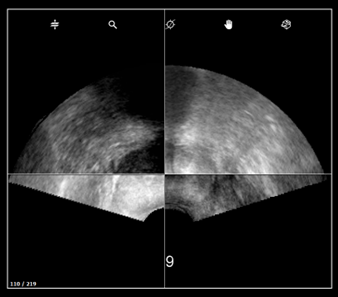

2. Misuse during 3D acquisition

a. The prostate is incomplete

Probe rotation - in transrectal approach, for biopsy to be perform to the left side of the prostate, the needle guide shall be placed on the left side of the patient.

b. Compare settings with panorama’s setting

- US depth must remain the same between the panorama and the following biopsy acquisitions.

- Panorama settings must be the same as the acquisition settings to have a good image fusion.